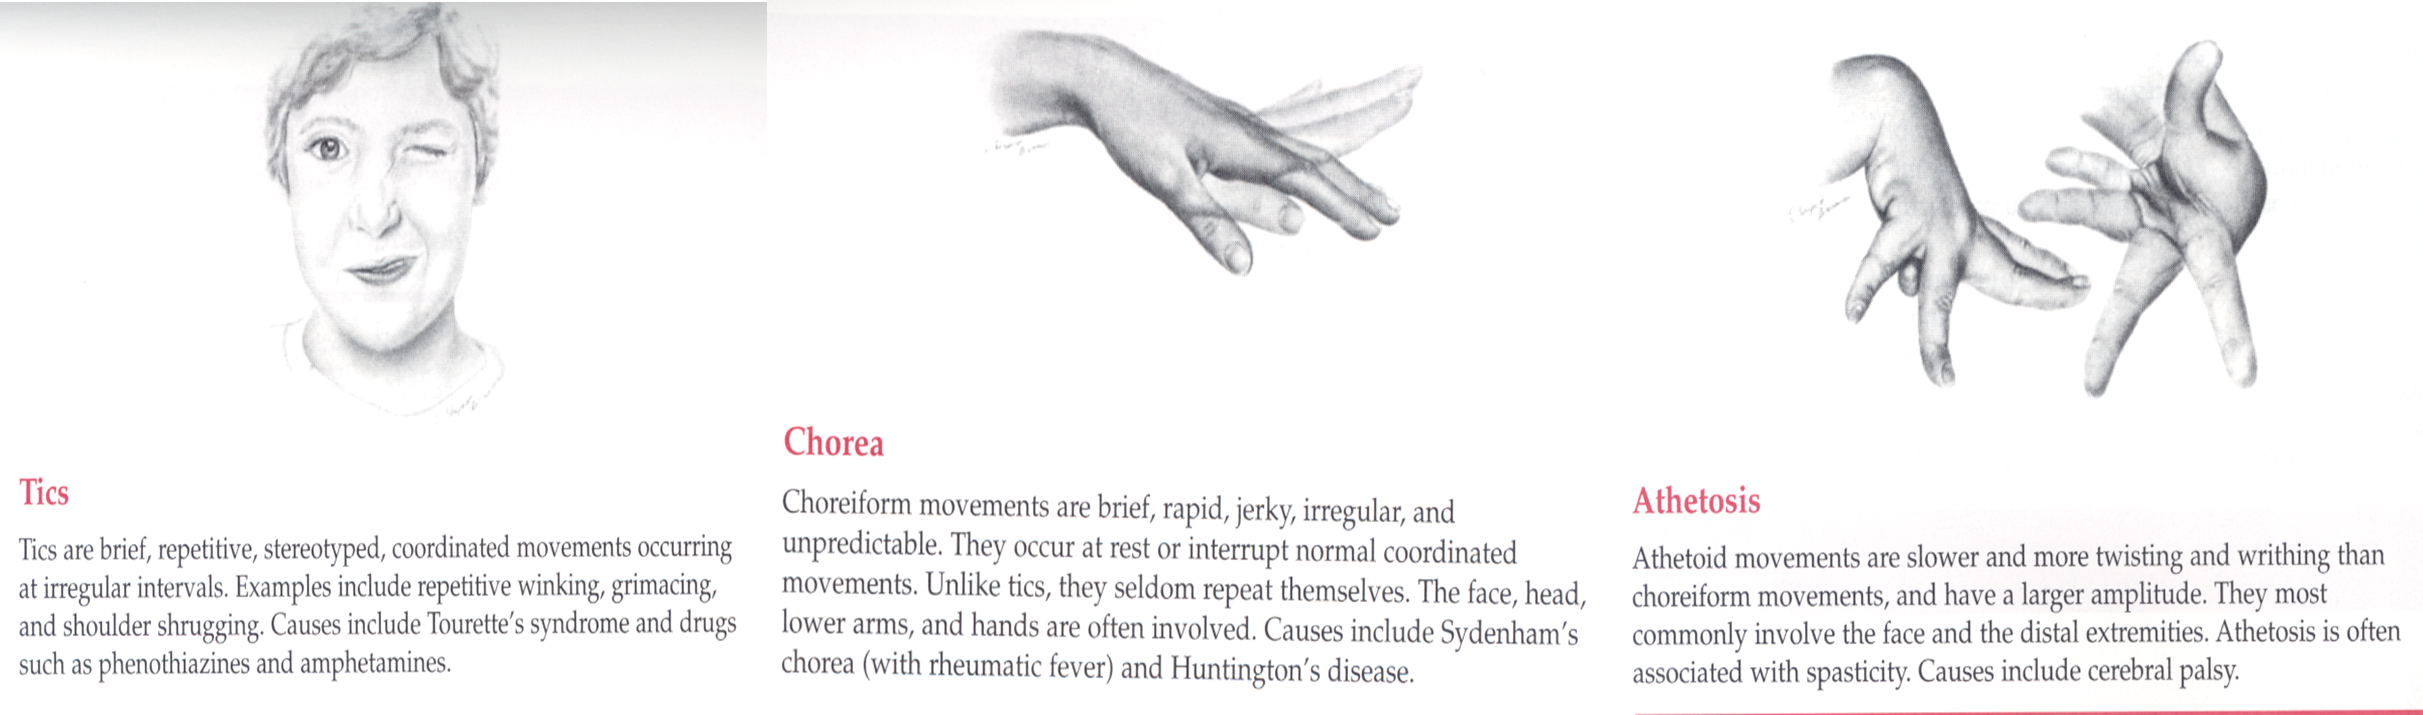

Involuntary movements

- location, quality, rate, rhythm, amplitude

Abnormal Movements

Cerebellar vs. Basal Ganglia lesions

| Region | Signs and Symptoms |

|---|---|

| Cerebellar | - Awkwardness of intended movements |

| - Intention tremor | |

| - Ataxia | |

| Basal Ganglia | - Involuntary movements |

| - Resting tremor | |

| - Chorea | |

| - Athetosis | |

| - Hemiballismus |